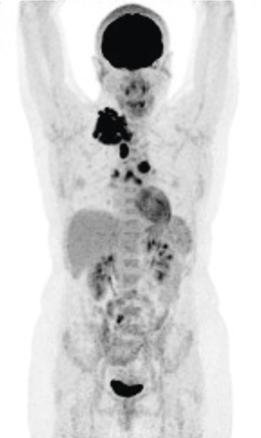

TEP/Scanner lors du bilan initial d'une patiente de 31 ans présentant un lymphome de Hodgkin montrant un hypermétabolisme supra diaphragmatique avec également une atteinte splénique et des ganglions sous diaphragmatiques.